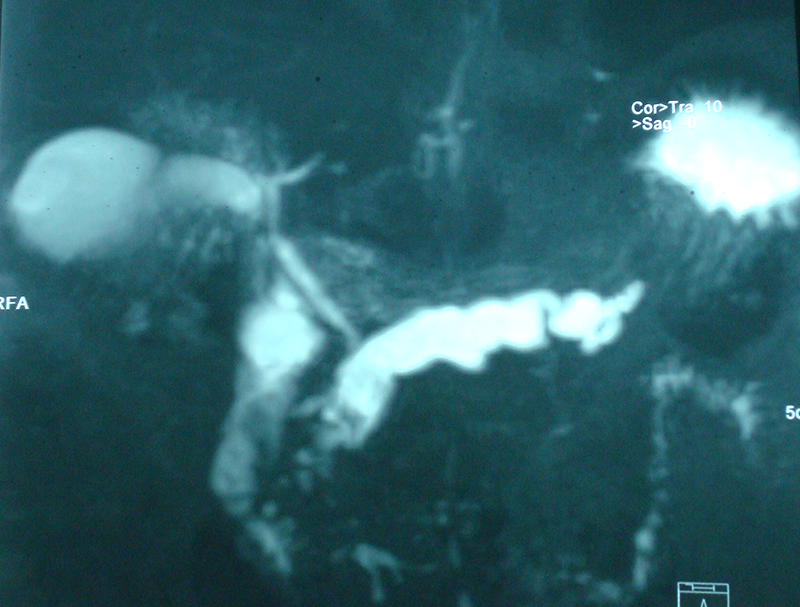

30 year old young lady with chronic pancreatitis, narrowing (stricture) of the pancreatic duct in the head and tail of pancreas and obstructing stone in the tail portion of the pancreatic duct presented to us with a recent attack of mild acute pancreatitis. She had undergone pancreatic duct stenting 3 times before this and stent migrated out of the duct at the last time following which she had acute pancreatitis. She was thoroughly evaluated with CT scan and MRI of abdomen. It showed that the duct had dilated irregularly in head and body of the pancreas and a stone was lodged in the tail. So she had disease both in the head and tail. She underwent a distal pancreatosplenectomy for the tail disease and a pancreaticojejunostomy (Head coring—Frey procedure) for the disease of the head and body of pancreas. She recovered well however the recovery was prolonged due to intra-abdominal infection caused by organisms in the infected pancreatic fluid. Infections originated from the pancreatic stents, were resistant to routine antibiotics and needed expensive drugs for infection control.